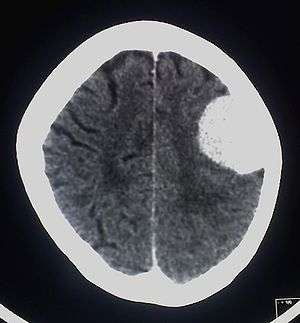

| A contrast-enhanced CT scan of the brain, demonstrating the appearance of a meningioma | |

Meningiomas are visualized readily with contrast CT, MRI with gadolinium,[14] and arteriography, all attributed to the fact that meningiomas are extra-axial and vascularized. CSF protein usually is elevated if lumbar puncture is attempted.